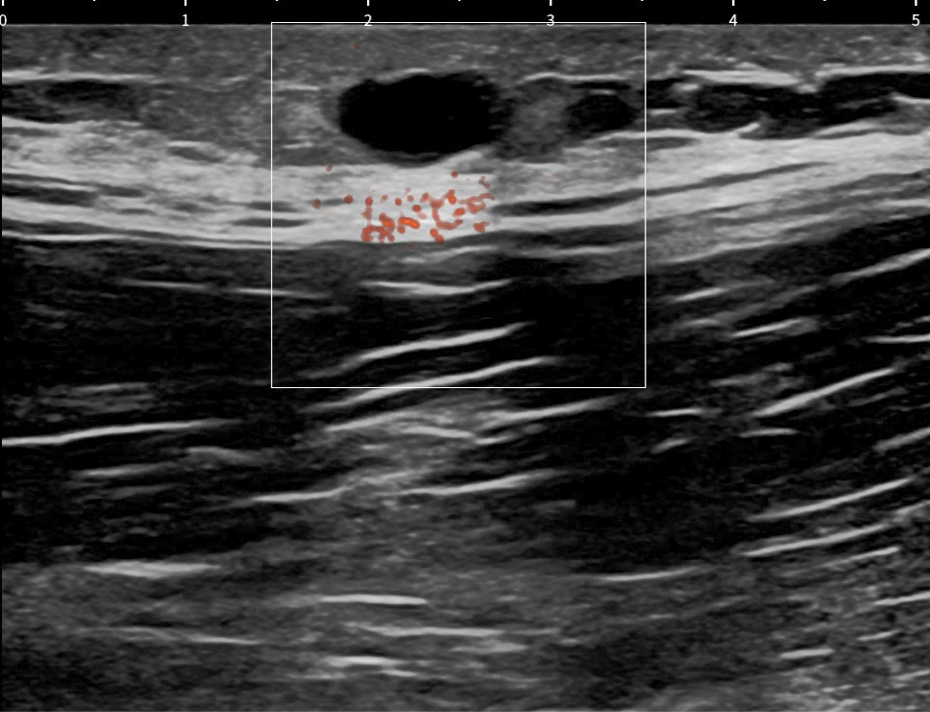

Hallazgos ecográficos

Lesión hipoecogénica de unos 13 x 9 mm, bien delimitada con refuerzo acústico y artefacto de borde compatible con quiste epidérmico.

Se planifica cirugía menor en Atención Primaria y se extirpa una vez localizado el pedículo vascular para evitar sangrado. Se envía material extirpado a anatomía patológica con resultado de quiste epidérmico.